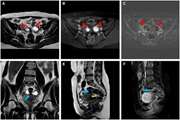

Refining MRI protocols for endometriosis: a comparative study of abbreviated and full MRI sequences 1404/01/17 - 08:55

Advanced MRI prediction model for anatomical site identification in uterine carcinoma: enhancing diagnostic accuracy 1404/01/16 - 09:57